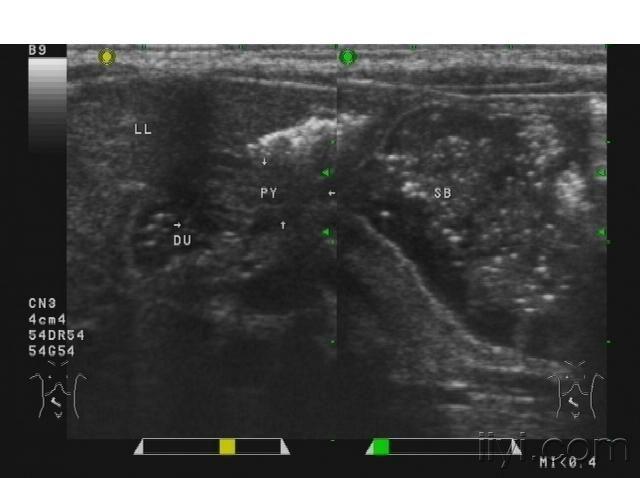

典型病例--幽门肥厚梗阻!

图片尺寸792x593